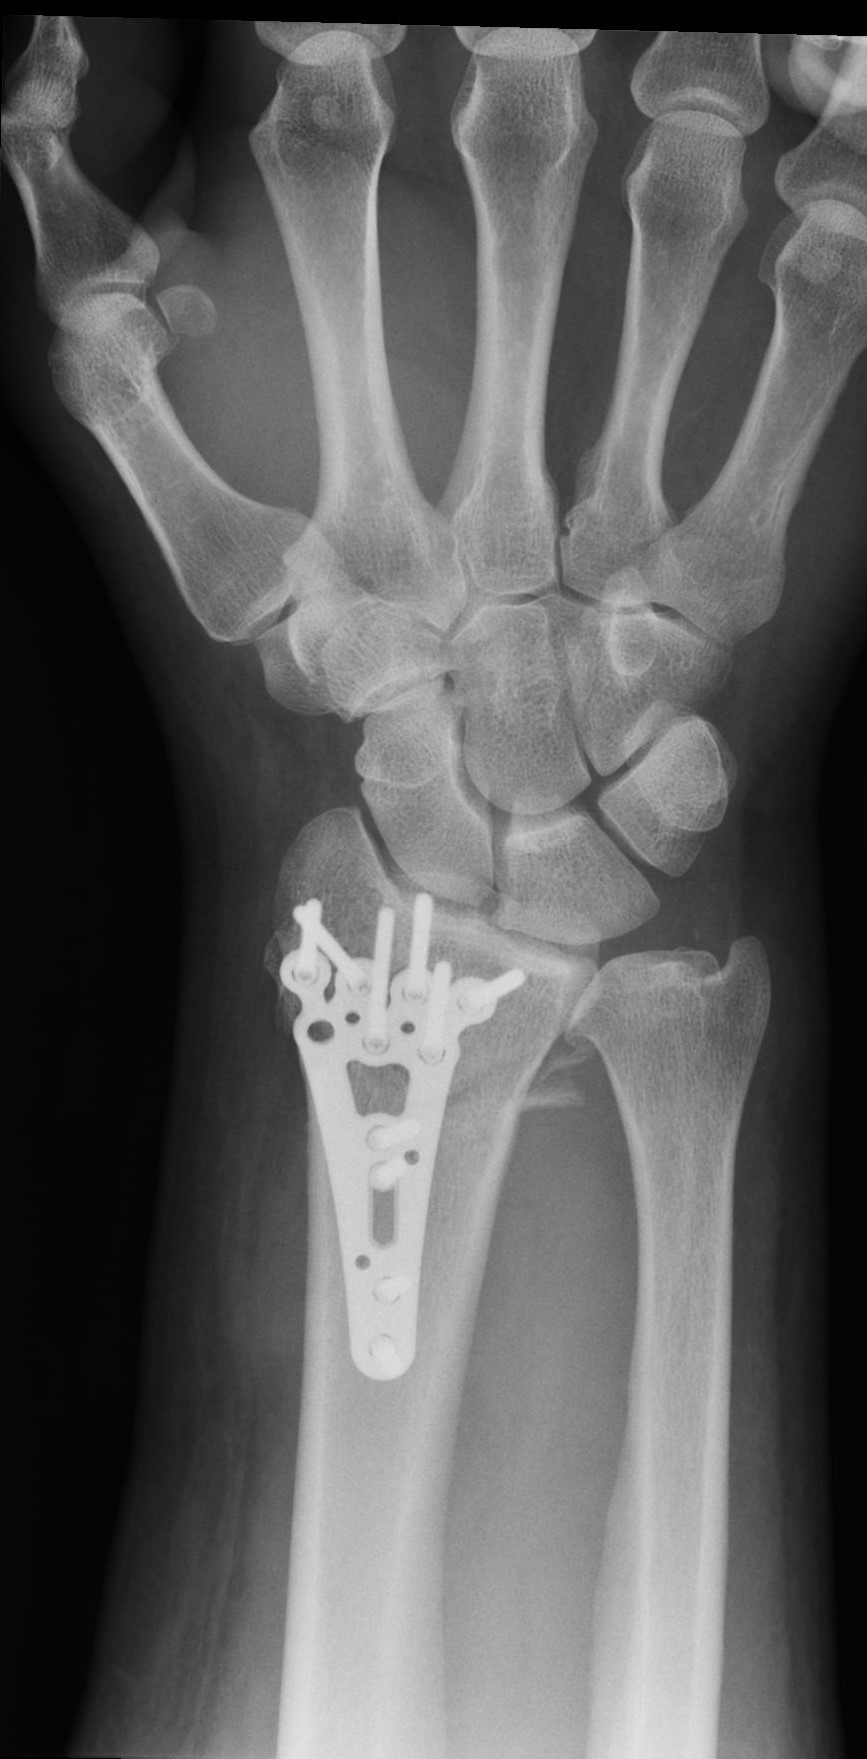

High-energy distal radius fractures are characterized by significant displacement of bone fragments, articular surface damage, and ligamentous injury. Tendon interposition between bone fragments occurs very rarely. In this report, we present a case of a complex distal radius fracture in which intraoperative findings revealed interposition of the flexor digitorum superficialis tendon of the index finger beneath one of the fracture fragments. The exceptional rarity of this situation prompted the authors to report this case.